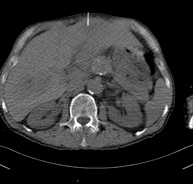

- Abdomen CT

Diagnostic test that involves obtaining high-definition anatomical images of the abdomen (liver, gallbladder, bile duct, pancreas, spleen, stomach, intestines, kidneys, vascular structures, bladder, uterus and ovaries, etc.) using CT (computed tomography) equipment. These images are then studied at a workstation capable of producing two-dimensional reconstructions in different spatial planes, and also 3D (volumetric) reconstructions. Most studies require the use of iodinated contrast to improve image definition.

- Abdominal and pelvic CT

Diagnostic test that consists of obtaining high-definition anatomical images (bone structures, vascular structures, liver, pancreas, gallbladder, kidneys, adrenal glands, spleen, small and large intestine, bladder, uterus and ovaries, prostate and seminal vesicles, ureters, etc.) using CT (computed tomography) equipment. Most studies require the use of iodinated contrast.